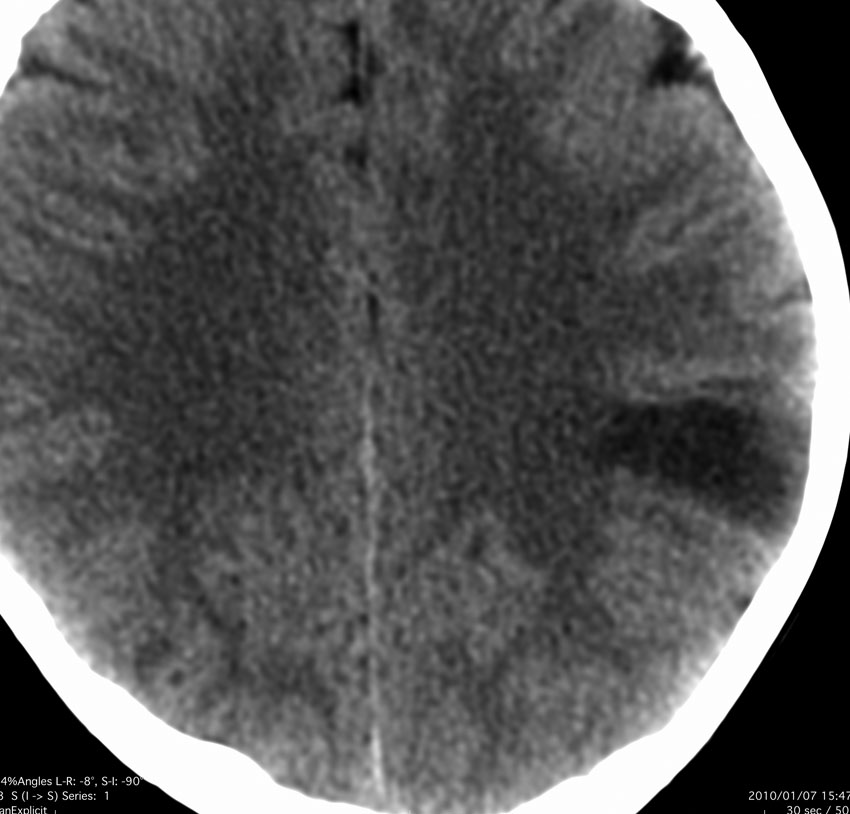

病理は,粘液気質を背景に小型円形の核を有する細胞が増殖し,肺胞用構造を呈していました。その中にやや大型の神経細胞が多数混在するものです。

術前発作期間が長いと症状の回復が不良であるという残念な例でもありました。